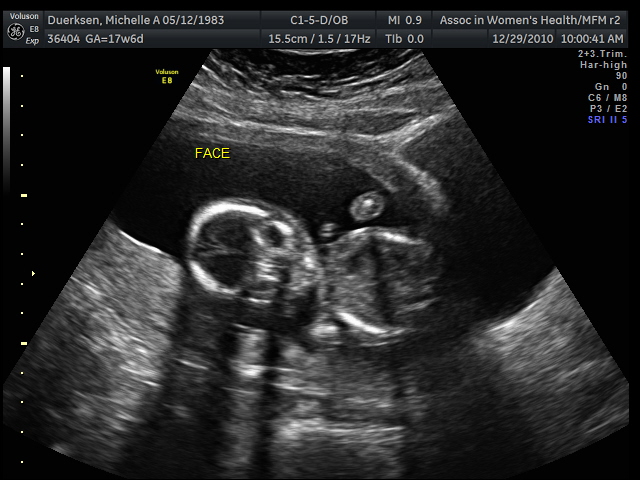

And now and forever, our Duerksen girl will have her privacy violated. Yes, if you can make it out, this is a shot from behind, with her feet extended and crossed at the ankles with nothing hanging in between. (Hence how we knew it was a girl.)